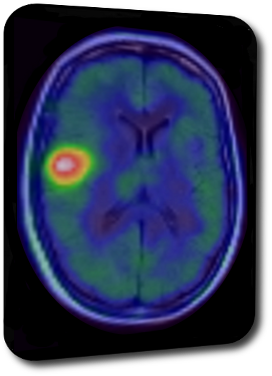

Neuroonkologie

Prof. Dr. Stefan Bittner

Universitätsmedizin Mainz